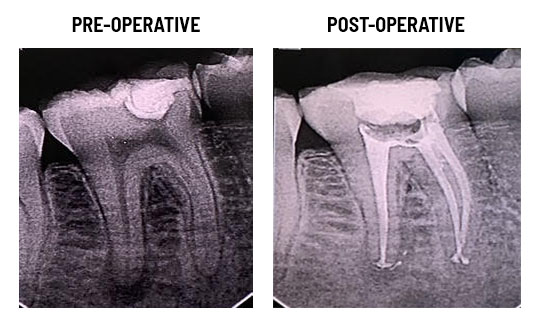

Before and After Images

Our Root Canal Treatment Experiences

Root Canal Therapy

X-rays are taken to determine the extent of the damage. Local anesthesia is administered to numb the area.An opening is made in the crown of the tooth to access the pulp.The infected or damaged pulp is removed, and the root canals are cleaned and shaped The cleaned canals are filled with a biocompatible material, usually gutta-percha.